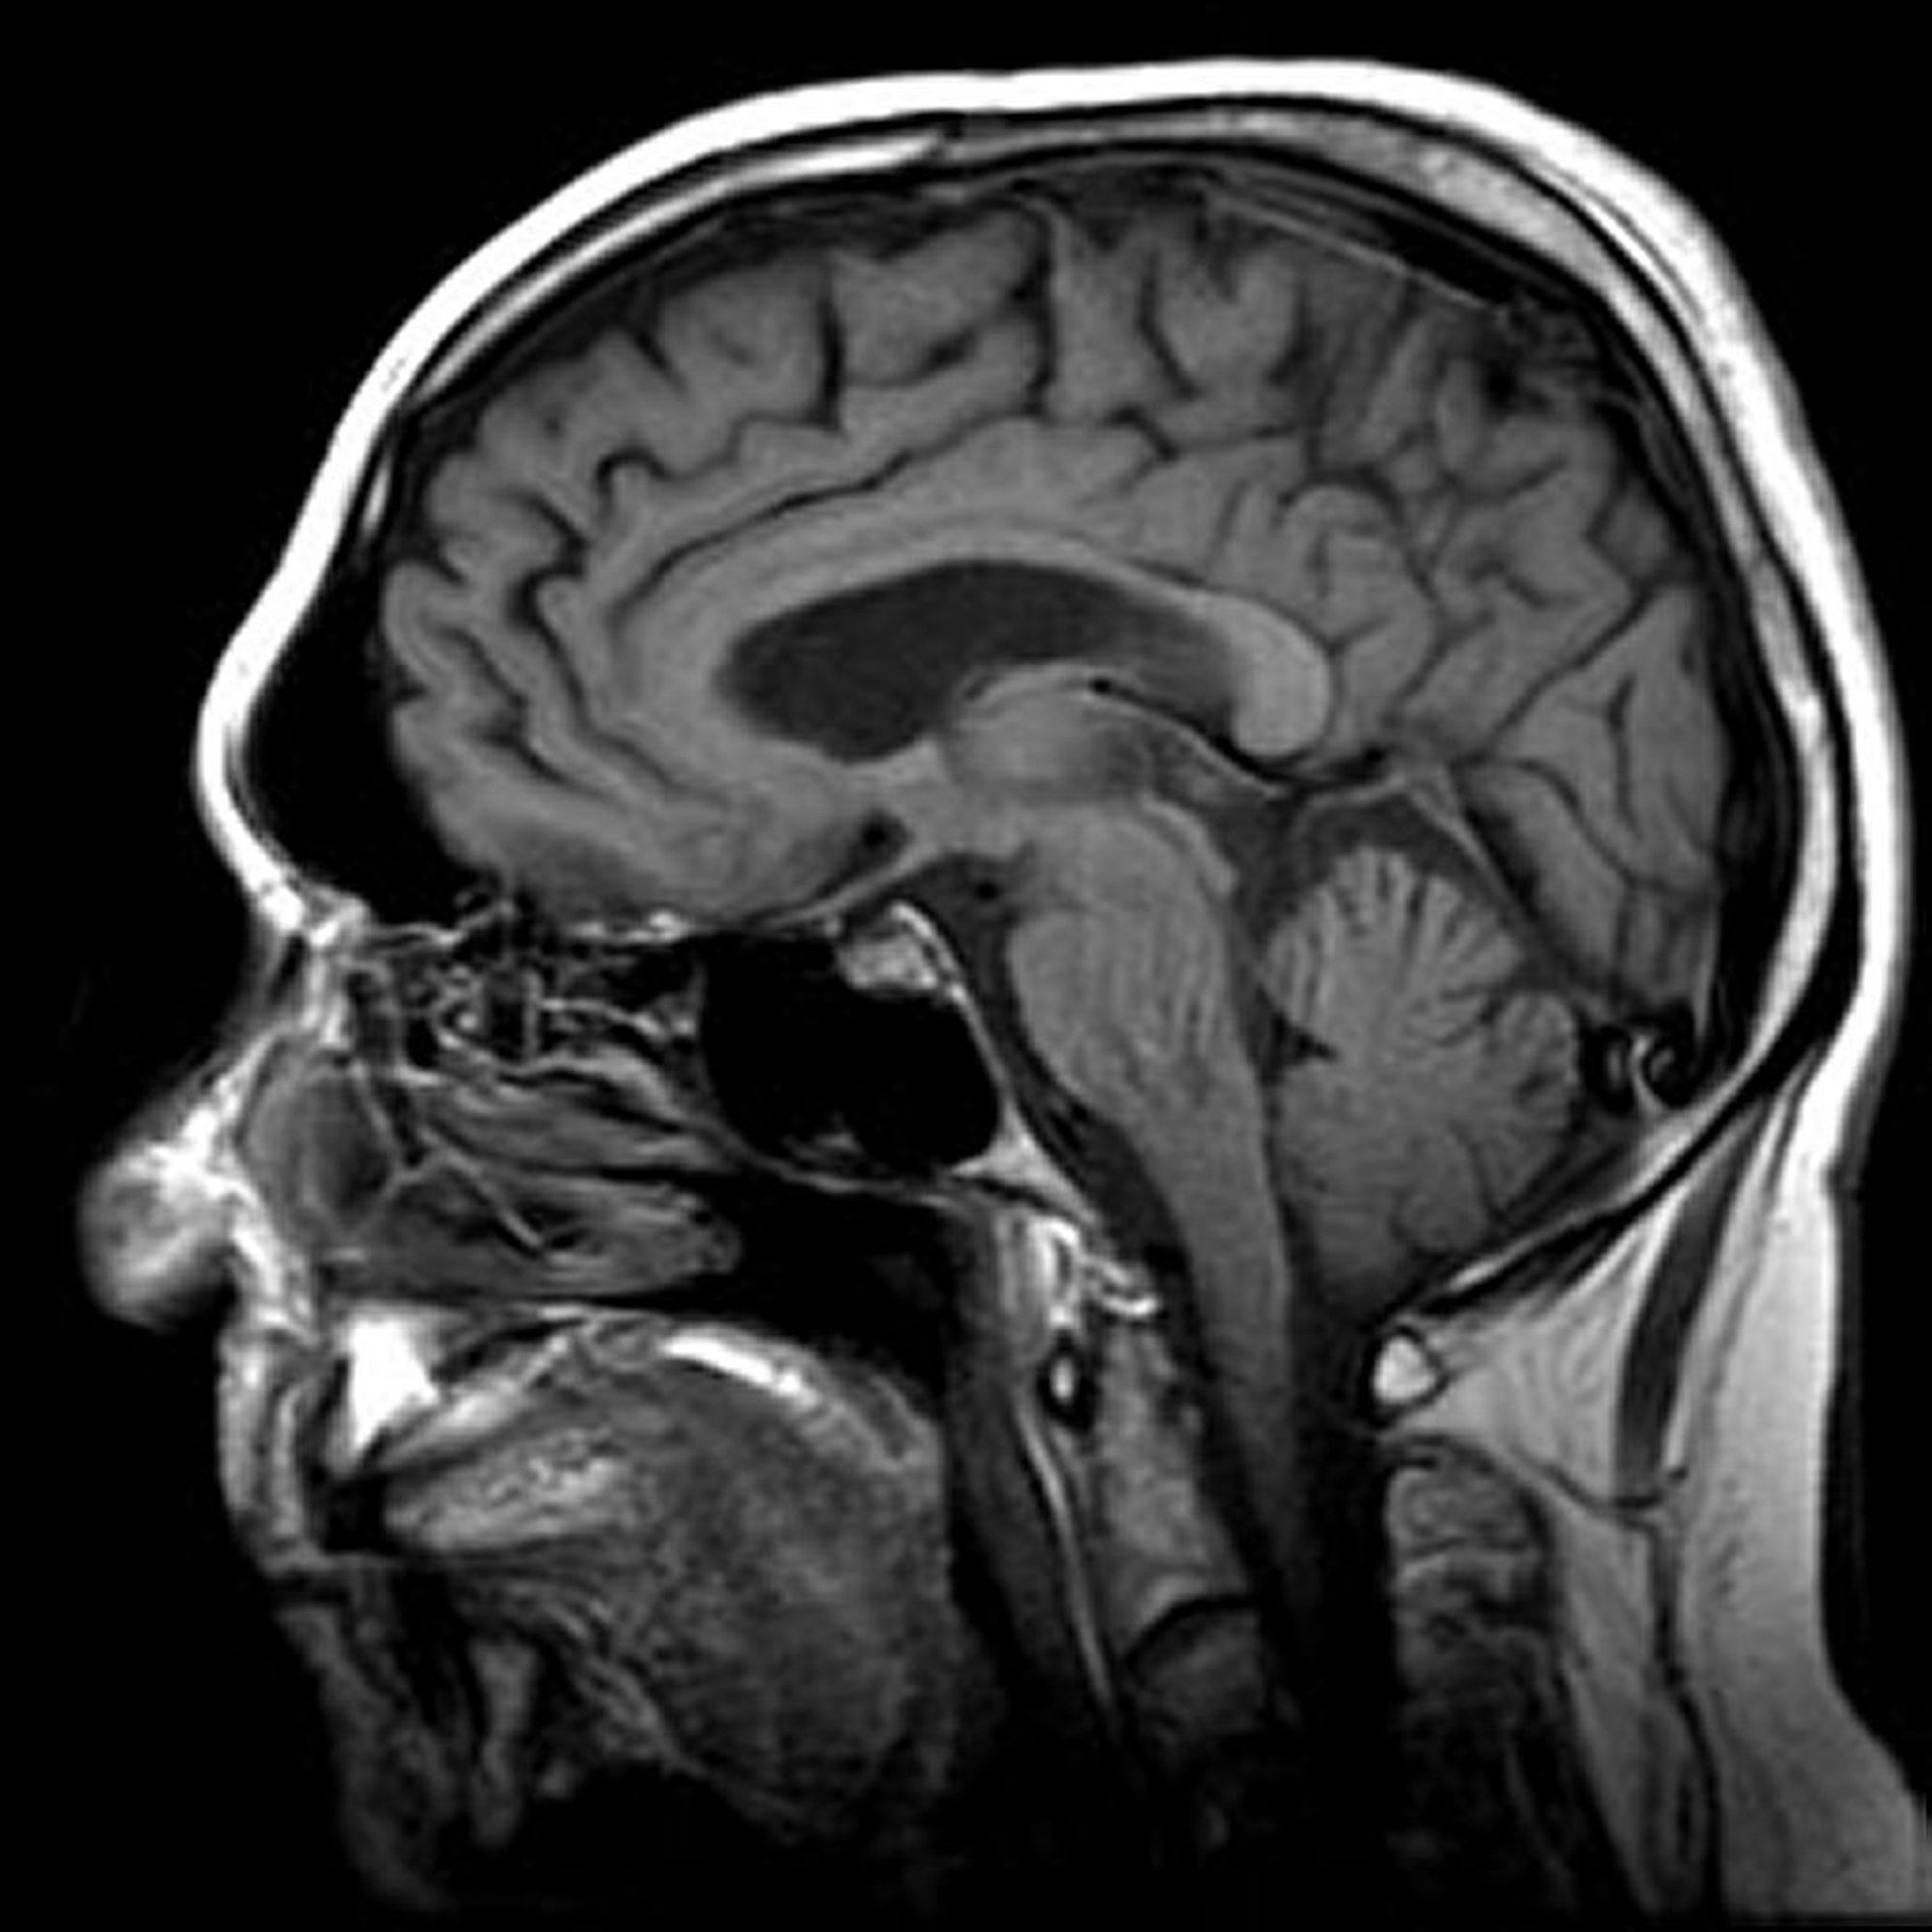

Magnetresonanztomografie (MRT) des Gehirns

Bild von Dr. med. Jon A. Jacobson.